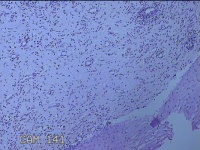

宫颈6点、12点组织

性别

女

年龄

33岁

临床诊断

人乳头瘤病毒感染

一般病史

发现HPV18,其他12种阳性近一月。

标本名称

大体所见

1.“宫颈6点组织”:灰白粉红色组织0.5x0.3x0.2cm一块。 2.“宫颈7点组织”:灰白暗红色组织0.8x0.3x0.2cm两块。

图2